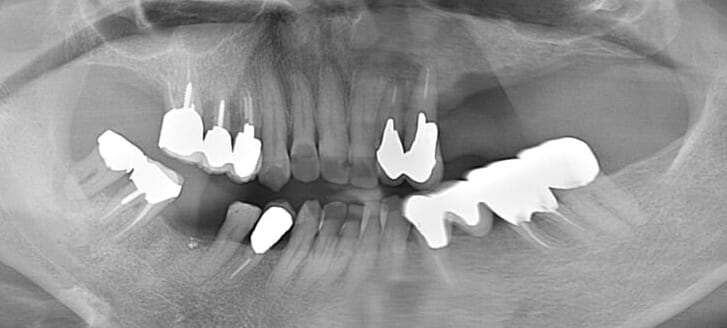

治療後 ※治療箇所は、画像右上

インプラントを6本入れるのではなく、インプラント3本(土台)の上に上部構造としてセラミックの歯(5本)をブリッジにする、インプラントブリッジをご提案しました。

CT撮影と精密なシミュレーションにより、インプラント治療は問題なく終わり、痛みや腫れもほとんどなく大変喜んでいただきました。

また「治療後何年経っても自分の歯のように硬いものでも何でも噛める。インプラント治療をして本当に良かった!」というお声もいただいています。